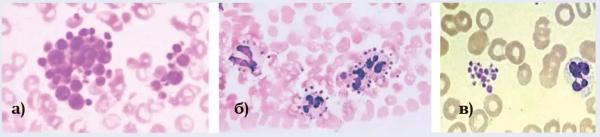

Применявшиеся ранее подсчет количества тромбоцитов в мазках крови (метод Фонио, при котором тромбоциты подсчитывают в окрашенных мазках крови на 1 000 эритроцитов), и подсчет количества тромбоцитов в камере Горяева не являются стандартизированными тестами, имеют высокую погрешность и не рекомендованы, поскольку в мазке могут иметь место такие морфологические феномены, как тромбоцитарный сателлизм (оседание тромбоцитов на поверхности лейкоцитов), скопления тромбоцитарных агрегатов, наличие гигантских тромбоцитов (см. рис. 2).

Рисунок 2. Морфологические феномены тромбоцитов в мазке крови: а) гигантские тромбоциты; б) тромбоцитарный сателлизм; в) скопление тромбоцитов.